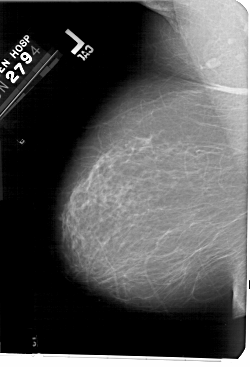

A_1561_1.LEFT_MLO

LEFT_MLO LINES 5491 PIXELS_PER_LINE 3736 BITS_PER_PIXEL 12 RESOLUTION 43.5 NON_OVERLAY